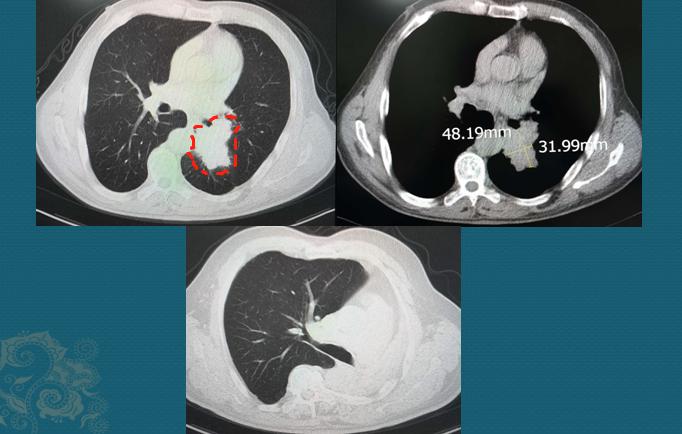

这是一位64岁男病人,老烟民,牙齿都是焦黄的,反复咳嗽、痰多40天,胸闷10天,CT发现左侧中心型肺癌:

下面的图是手术后3.5年复查,左肺全切,没有复发

中心型肺癌手术要慎重,需要术前充分评估,除了排查有无远处转移之外,还要重点观察对肺门血管、气管的侵袭范围,判断有无手术条件。

随着胸外科各种微创技术的进步,很多禁区也在不断突破!豪大夫最佩服的就是胸外科医生,因为肺癌发病率最高,而每一个小突破都能给成千上万的病带来新希望!这位病人做了左侧全肺切除,昨天回来复查,已经3年半了,没有复发。